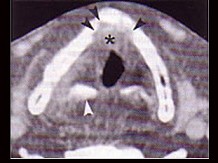

4.下面是一颈部CT图,其中结构标志不正确的是  (    )

正确答案:D

6.CT检查见下图,进一步的检查是  (    )